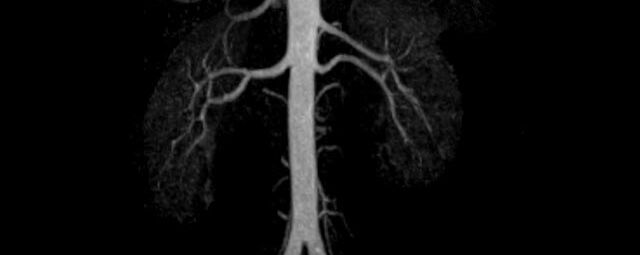

• Bauchgefäße

• Erfassung und Verlaufskontrolle bei arteriellen Aneurysmen (Aussackungen der Arterien), vor allem der Bauchaorta

• Darstellung von Gefäßengen an Nierenarterien, Baucharterien und Becken-/Beinarterien

MR-Angiografie (MRA)

• MR-Angiographie mit Kontrastmittel

• Erfassung arterieller und venöser Gefäße/Bypässe aller Körperregionen mit 3D-Rekonstruktion